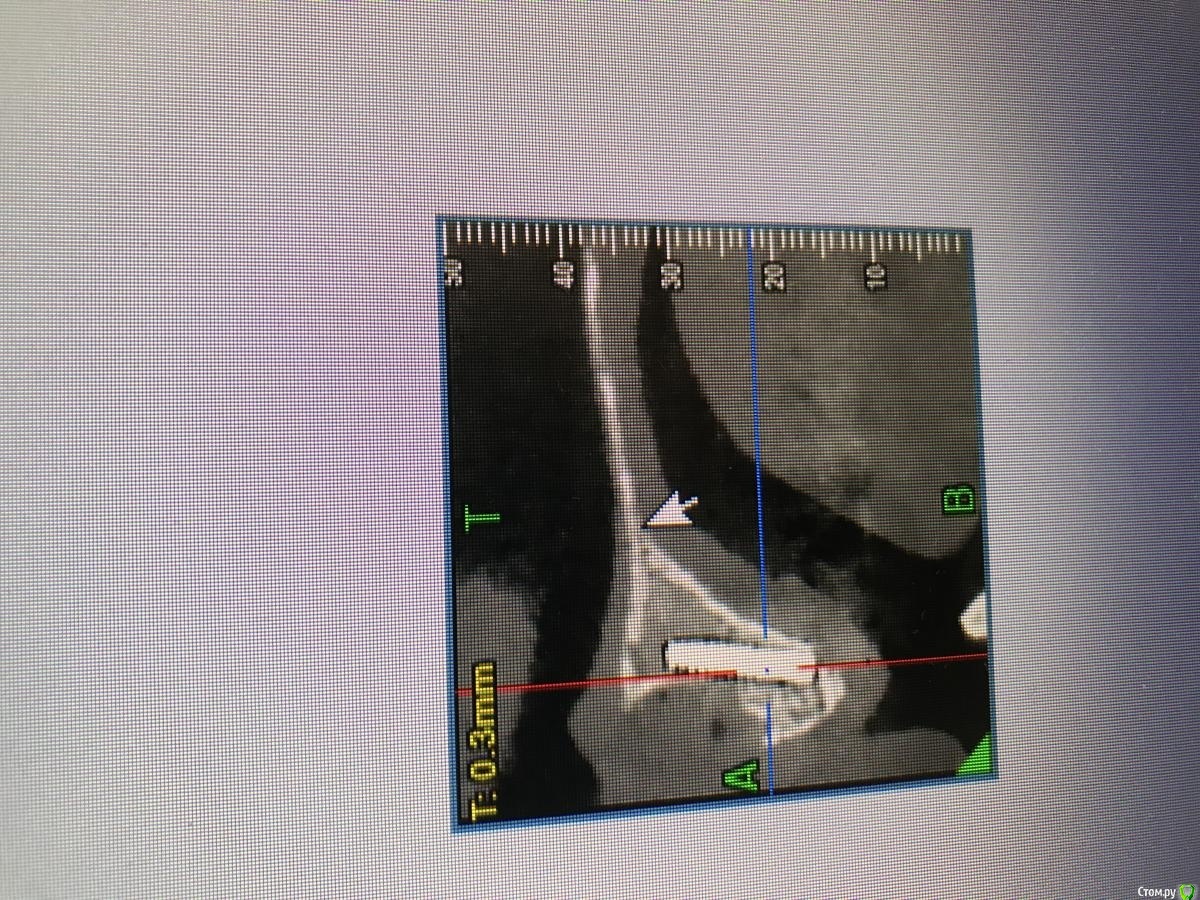

MakovskyAlexandr Опубликовано 8 октября, 2020 Поделиться Опубликовано 8 октября, 2020 Здравствуйте, люди добрые, подскажите пожалуйста.Удалены 2 Корня(21 и 12). Пациентка отказалась от трёх коронок, изъявила желание именно двумя восстановить.Удалены корни - установлены импланты анкилоз А3.5 11 и 14 мм.Выполнена костная пластика , материал ограждён мембраной- все по классике, мембрана фиксирована пинами. Я так понимаю произошло смещение материала( то от гематома, то ли отёк такой). Как быть дальше? Ждать интеграции и подсаживать потом аутотрансплантат?Спасибо огромное. Ссылка на комментарий

колесников Опубликовано 8 октября, 2020 Поделиться Опубликовано 8 октября, 2020 Анкилос надо было топить хорошо и грузить. Мне кажется или для 11 нет места? 1 Ссылка на комментарий

MakovskyAlexandr Опубликовано 8 октября, 2020 Автор Поделиться Опубликовано 8 октября, 2020 Анкилос надо было топить хорошо и грузить. Мне кажется или для 11 нет места?Для 11 нет места. Ссылка на комментарий

Александр07 Опубликовано 31 октября, 2020 Поделиться Опубликовано 31 октября, 2020 И А14 анкилоз нет смыла ставить а9.5 даже А 8 работает без проблем в таких длинных нет смысла на этой системе точно Ссылка на комментарий